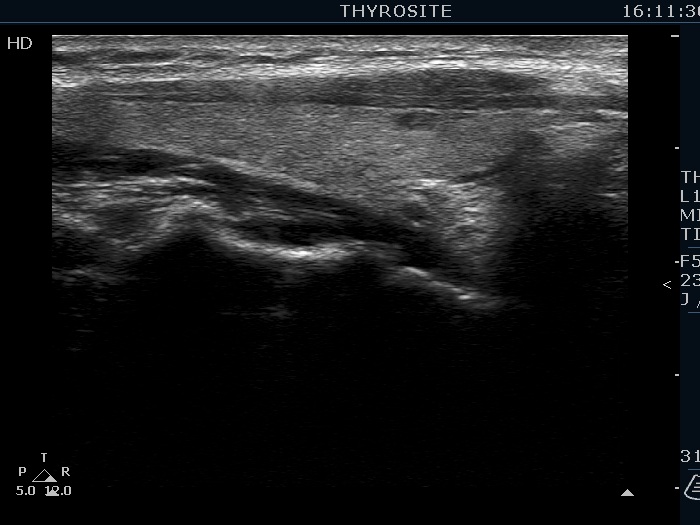

Ultrasonography. The thyroid was echonormal. There were several hypoechoic nodules in the left lobe. The middle one had back wall cystic figures. There were 3 or four discrete, deeply hypoechoic lesions above and lateral to the left lobe in the neck. One of them presented with a hilum-like figure while the others lacked hilum.

The lymph nodes had a non-typical presentation. They lacked a regular hilum.